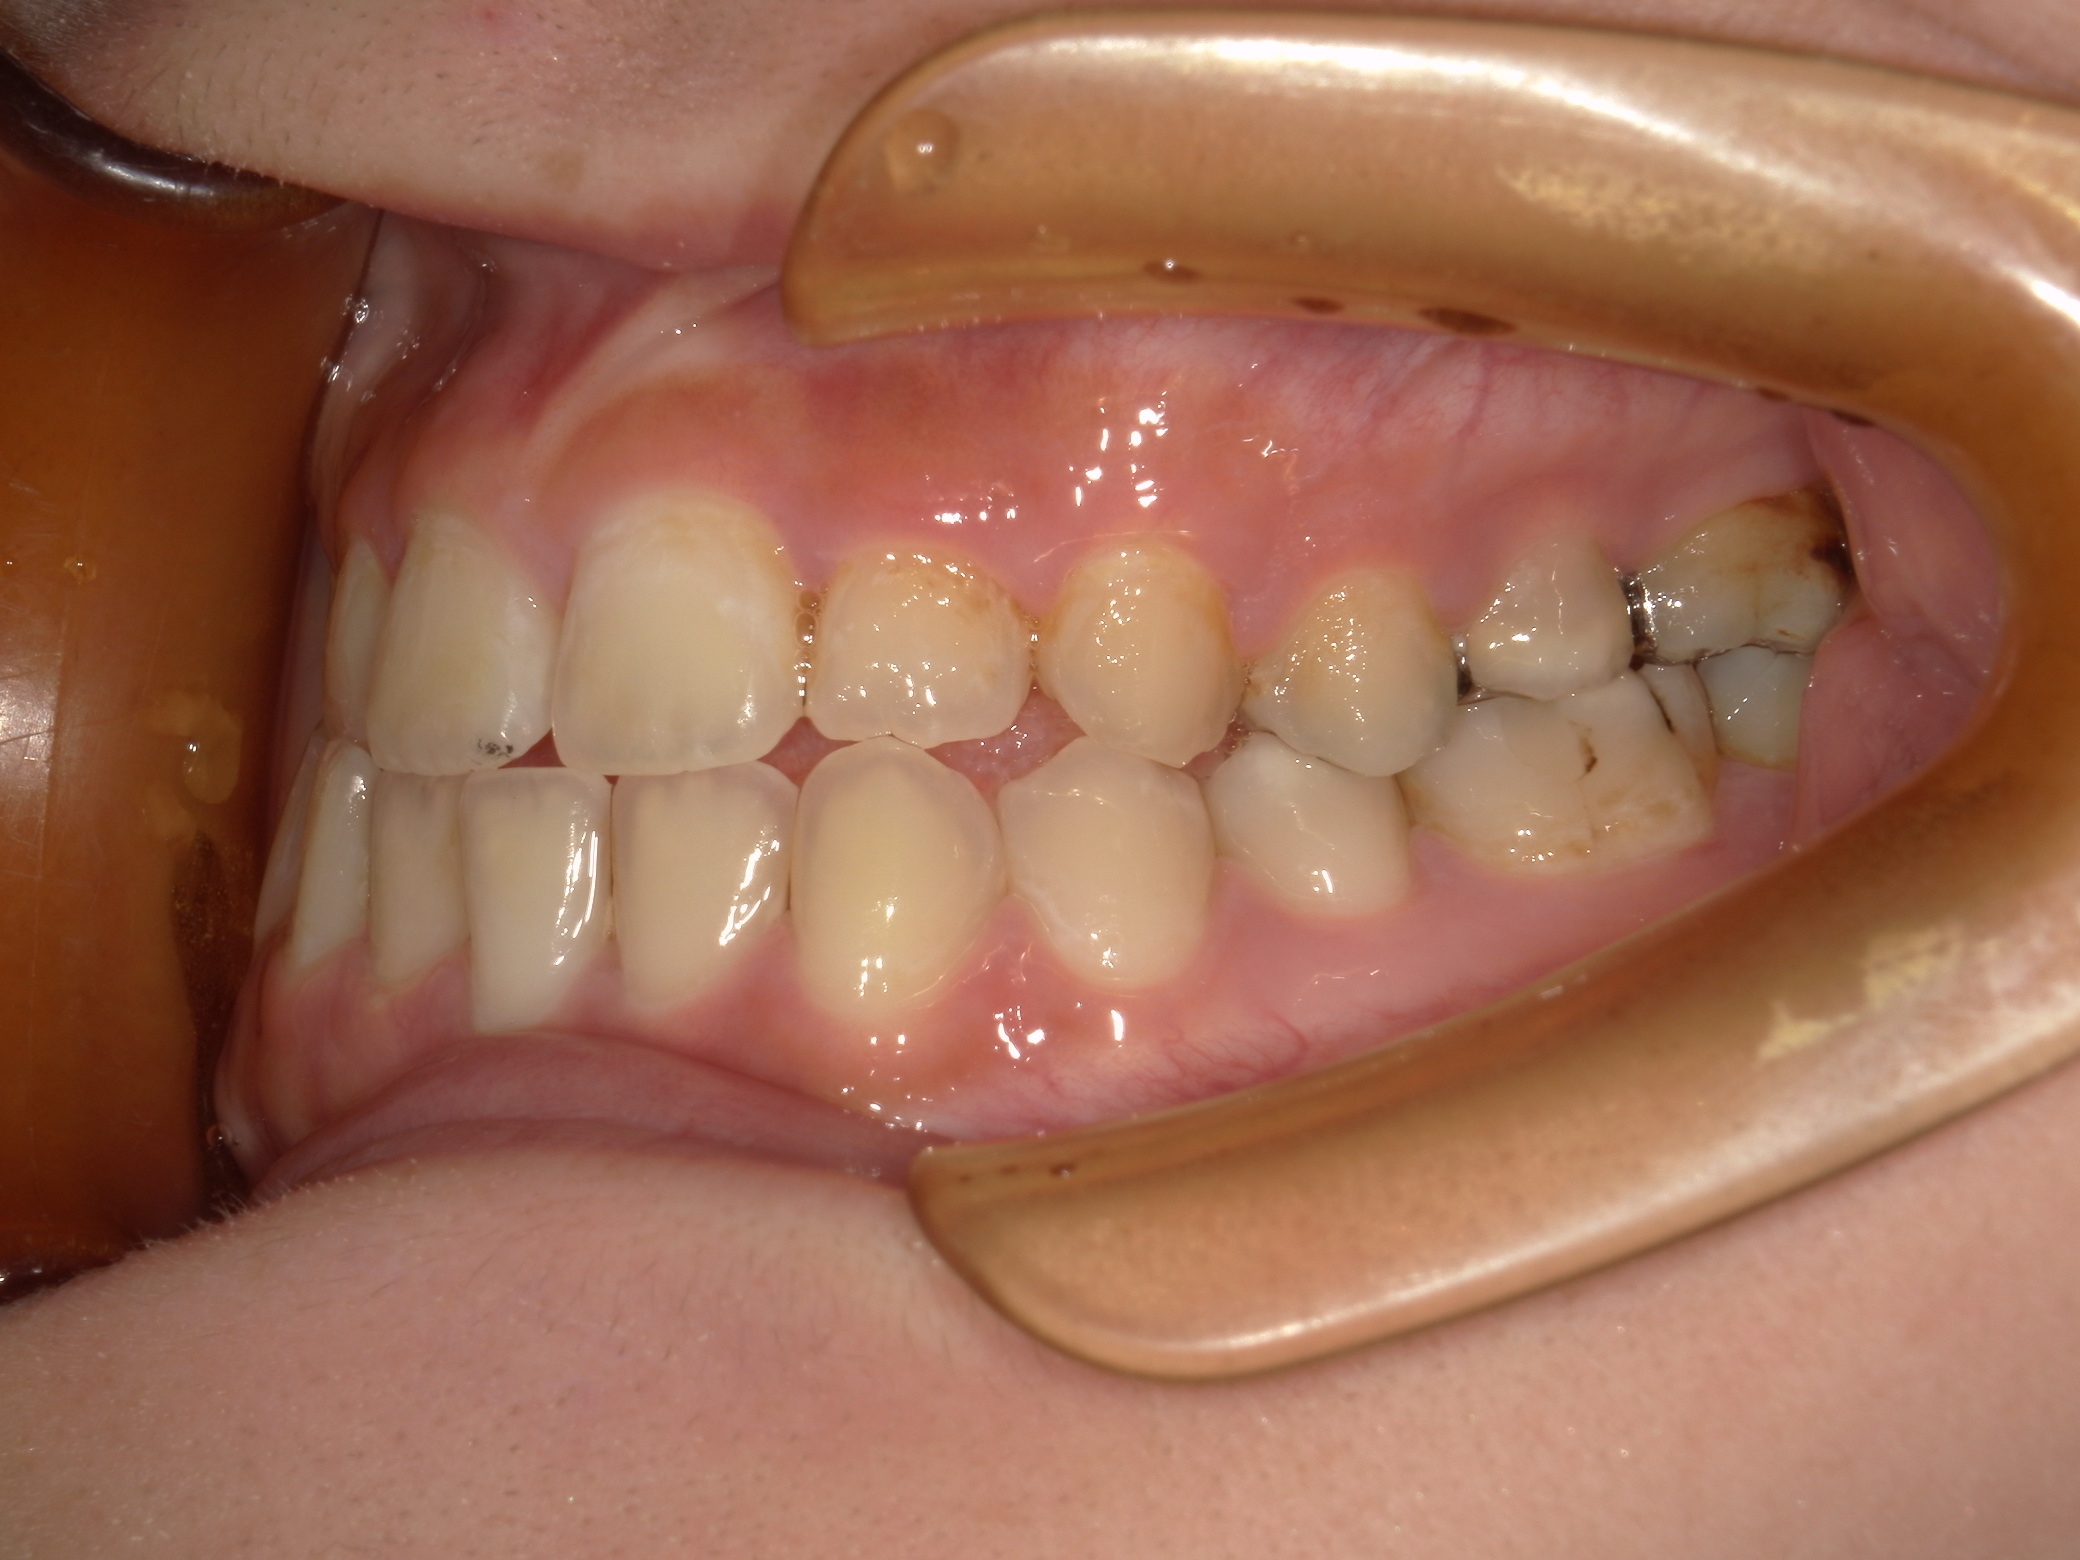

口内上

治療前

治療後